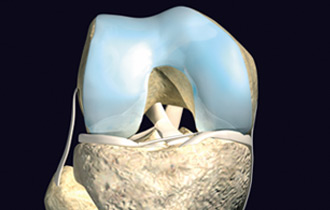

中英合资——关节动力安达(天津)生物科技有限公司是亚太地区首家以研究、生产自体软骨组织细胞移植产品为主的高科技生物企业。具有世界先进水平的自体软骨组织细胞体外培养、移植技术和产品,并拥有自主知识产权,其核心产品包括: CaReS®(软骨再生系统)、CFI(软骨栓)、NuCell(脊椎间盘修复系统)等。公司位于天津港保税区空港物流加工区环河南路,总投资2亿元人民币。

公司拥有的系列产品均采用生命科学领域细胞工程学和工程学的原理与方法,用于软骨相关疾病的治疗,适用于医疗机构骨科临床急、慢性关节软骨缺损疾病的早期修复和治愈性治疗,也可应用于脊椎间盘的软组织损伤细胞修复。是研究和开发用于修复和维护或增进人体各种组织器官损伤后功能和形态的一个边缘性新学科,属于当代前沿科学。

CaReS®(软骨再生系统)等生物组织工程技术和产品的临床应用,将为软骨缺损疾病治疗提供全新的观念并进一步丰富针对软骨缺损疾病的治疗方法,提升骨科临床的治疗水平,与世界接轨并同步发展。通过该技术和产品的临床应用,使广大的患者与欧美国家同步享受高科技生物组织工程技术与产品带来的福祉,提高生活质量,造福于社会。